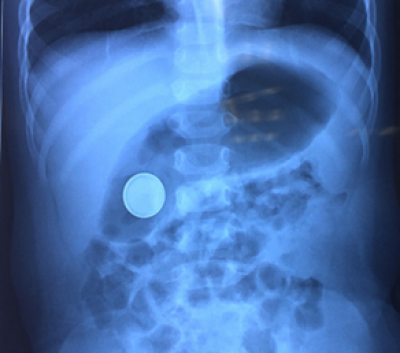

Nội soi thực quản dạ dày lấy dị vật

Nuốt dị vật là lí do nội soi can thiệp khá phổ biến trong cấp cứu nhi khoa. Nội soi ống mềm can thiệp dị vật là một phương pháp hiệu quả và an toàn.